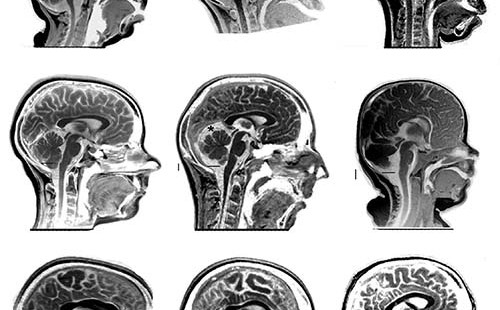

Acquire Brain Injury (ABI) is an umbrella term used to categorise a wide range of brain injury conditions that occur aft...